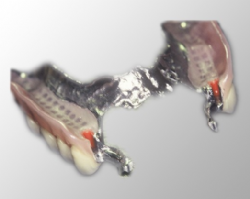

Die Teilprothese ist ein herausnehmbarer Zahnersatz. Er wird an

den vorhandenen Zähnen mit Klammern befestigt. Die Befestigung kann auch mit

gleichzeitig anzufertigenden Geschieben oder Teleskopkronen auf vorhandenen

Zähnen erfolgen, was oft schöner und für die Restzähne unter Umständen

schonender sein kann.

Die Teilprothese besteht aus einem Metallgerüst und Kunststoffteilen, sie ist

verhältnismäßig leicht erweiterbar, wenn weitere Zähne verloren gehen. Im

Vergleich zu festzementierten Brücken und zu Implantaten ist sie kostengünstig.